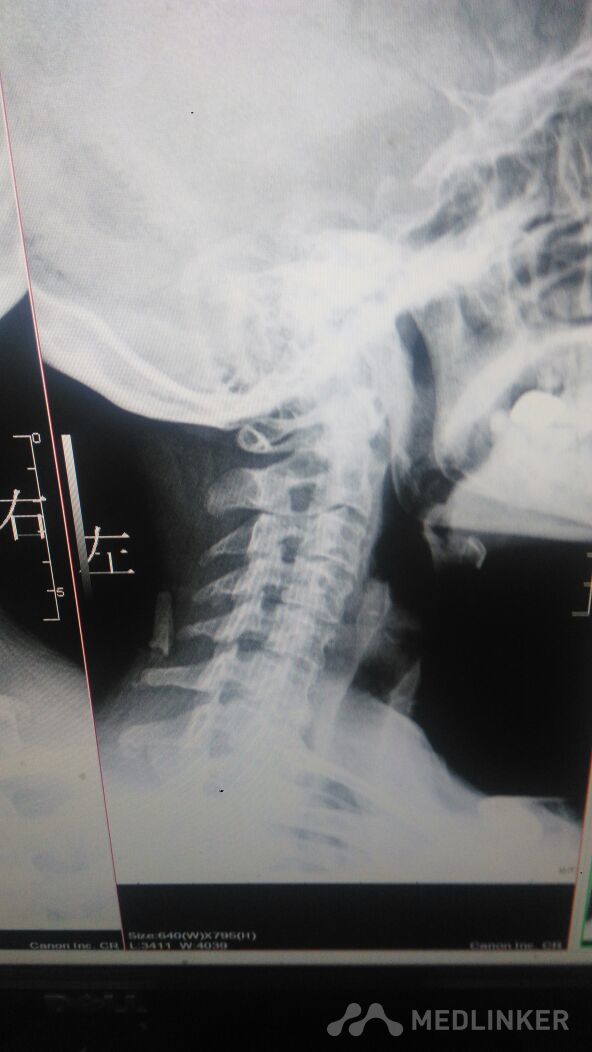

年轻人的颈椎病。很多见。

颈椎病

颈部疼痛,有长期看手术史。颈部压痛阳性,叩痛阴性。颈部旋转功能受限。

颈部疼痛,活动受限。年轻人。双手麻木。不能干重活。有的时候发昏。

年轻人的颈椎病,多为保守治疗。

长期低头看手机,造成颈部曲度的改变。颈椎间盘后突,神经根受压。姿势很重要。